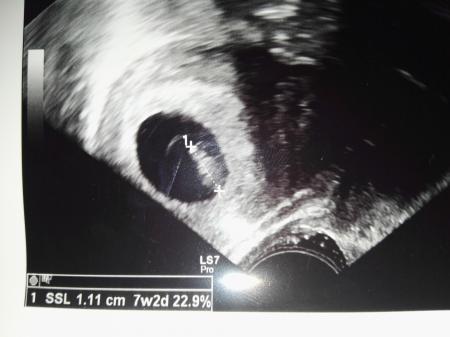

Unser kleines Krümelchen war am Freitag 1,11 cm groß, nun sind wir auf den nächsten Termin in vier Wochen, am 23.08 gespannt

Da sitzt das kleine Krümelchen in seiner großen Höhle ![]()